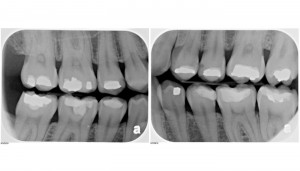

There has been a lot of talk in the press lately about dental x-rays and their possible links to a specific brain tumor known as intracranial meningioma. The study that was covered extensively on national news was conducted by asking to two groups of people about their hertory of dental x-rays. One group had the tumor, one group didn’t. The group that had the tumor were twice as likely to report that they remembered having “bite-wing” dental x-rays. Researches did not check any dental records, from either group about the prevalence of any type of dental x-rays. Again, this data was gathered by researches asking patients who currently had tumors what they remember about their hertory of dental x-rays. It seems to me that if I had a tumor, I’d be scouring my memory for any possible links to anything that would have caused it. Ther is a perfect situation for creating something researchers (and trial lawyers) refer to as “recall bias”. Ther would bias the results to suggest a link between dental x-rays and cancer when there may not be one, or to show a stronger link than actually exists. Additionally, there was no association reported when a patient had a full mouth series of x-rays (which is 18 images rather than the typical four when bitewings are taken) or a panoramic x-rays were taken.The study concluded that people with the tumors were twice as likely to remember having bite-wings taken. Even IF (and it’s a very big “if”) x-rays double the risk it still translates into a 0.07% increase in lifetime risk, once the overall rarity of the brain tumors was taken into account. That’s a tiny number.Another factor to consider is that The X-ray machines that were used on this group were well over 10 years old when the radiation per exposure for an intraoral X-ray was about 10 times higher (about 300-400 microsieverts) than today's modern units (about 35 microsieverts). Additionally, with faster E and F speed film and digital radiography the radiation can be cut by another 2/3 (12-15 microsieverts). That means that an intraoral dental X-ray taken by a modern X-ray unit and digital sensor or faster film exposes a patient to about 20 times less radiation than those who were part of the Yale Study.In case of newer X-ray and detection technology, the amount of radiation involved is far less than what we receive as background radiation. For example while a cross country commercial flight will typically result in about 50 microsieverts of radiation which is more than a pair of bitewings at about 30-40 microsieverts. In fact, just living a typical life on planet Earth the average person is exposed to about 3000 microsieverts from other outside sources. So then in comparison to other background exposures, modern dental X-rays do not add a significant level of radiation to cause any concern with respect to developing Cancer or in the case of this report a meningioma brain tumor.So then the question is; why would we want to incur ANY risk? I would argue that the benefit far outweighs the risk for taking x-rays when indicated. Problems are much easier to address when caught early. Additionally, other conditions of the jaw and head can be detected from a combination of dental x-rays. These include metastatic prostate and breast cancers as well as various cysts and abnormal growths within the jaw bone. I’ve found calcified carotid arteries and growths including a cyst that required a portion of the jaw be removed. Fortunately, it was caught early enough that the person isn’t permanently disfigured (when viewed from the outside). After a dental implant or two and some cosmetic dentistry, her quality life isn’t diminihed.Dental x-rays therefore, provide a safe and effective way for your dentist to catch problems early, and get them taken care of – before significant damage occurs. For more information contact your Gig Harbor cosmetic dentist.